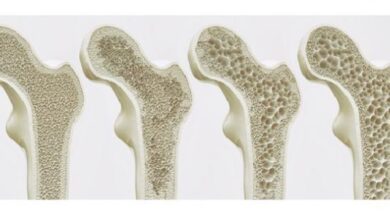

هشاشة العظام (بالإنجليزية: Osteoporosis)، أو تخلخل العظام أو مرض الهشاشة، هو المرض الذي يتمثل بقلة كثافة العظام وتلف بنيتها إلى درجة تجعل العظام هشة وقابلة للكسر، وحقيقة إنّ هذا المرض صامت بمعنى أنّه لا يُرافقه ظهور أعراض في العادة، فعادة ما يُكشف عنه عند حدوث كسر في العظام؛ إذ تكون العظام قد خسرت الكثير من بنيتها وقوتها على مدار عدة سنوات، وإنّ أكثر العظام تأثرًا بمرض الهشاشة عظام الرسغين والوركين وكذلك عظام العمود الفقري، وفي سياق الحديث عن هشاشة العظام يُشار إلى أنّ العظام هي أنسجة حيوية يُحافظ الجسم على قوتها من خلال تحطيم القديم منها والاستعاضة عنه بنسيج عظمي جديد،[١][٢] وأمّا بالنسبة لمدى شيوع مرض هشاشة العظام وانتشاره؛ فقد بينت مراكز مكافحة الأمراض والوقاية منها (بالإنجليزية: Centers for Disease Control and Prevention) نسب انتشار هشاشة العظام في الولايات المتحدة الأمريكية كما يأتي: نسبة انتشار هشاشة عظام عنق الفخذ والفقرات القطنية (بالإنجليزية: Lumbar vertebrae) تُقدّر بما يُعادل 5.1% بين الرجال الذين يبلغون الخامسة والستين من العمر فما فوق، في حين تقدّر نسبة انتشارها بـ 24.5% لدى النساء من نفس الفئة العمرية.[٣]

تمر العظام بدورة حياة بشكل مستمر، بمعنى أنّ الجسم يُحطّم القديم منها ويستعيض عن القديم بنسيج عظمي جديد، وفي الواقع يختلف معدل سرعة بناء العظم الجديد باختلاف عمر الإنسان، فمثلًا عندما يكون الإنسان في مرحلة الطفولة؛ فإنّ سرعة بناء العظم تكون أعلى بكثير من معدل هدمه، الأمر الذي يتسبب بزيادة الكثافة العظمية بشكل ملحوظ للغاية، ولكن عند بلوغ الإنسان العشرين من العمر فإنّ عملية بناء العظم وهدمه تُصبح أبطأ من ذي قبل، وفي أغلب الحالات تكون الكثافة العظمية في أعلى قيمة لها عند بلوغ الإنسان الثلاثين من العمر، وبعد ذلك وبتقدم الإنسان في العمر يُصبح معدل هدم العظام أسرع من معدل بنائه، وأمّا بالنسبة للعلاقة التي تربط ما سبق بهشاشة العظام فهي بسيطة، ويمكن إيجازها بقولنا إنّ فرصة المعاناة من هشاشة العظام تعتمد اعتمادًا كبيرًا على الكثافة العظمية القصوى التي وصلها المرء في سنوات شبابه، فكلما كانت الكثافة العظمية أكبر قلت فرصة الإصابة بهشاشة العظام، وإنّ ما يُحدد الكثافة العظمية القصوى للفرد هو العامل الوراثيّ وكذلك العرق الذي ينتمي إليه الشخص.[٥]